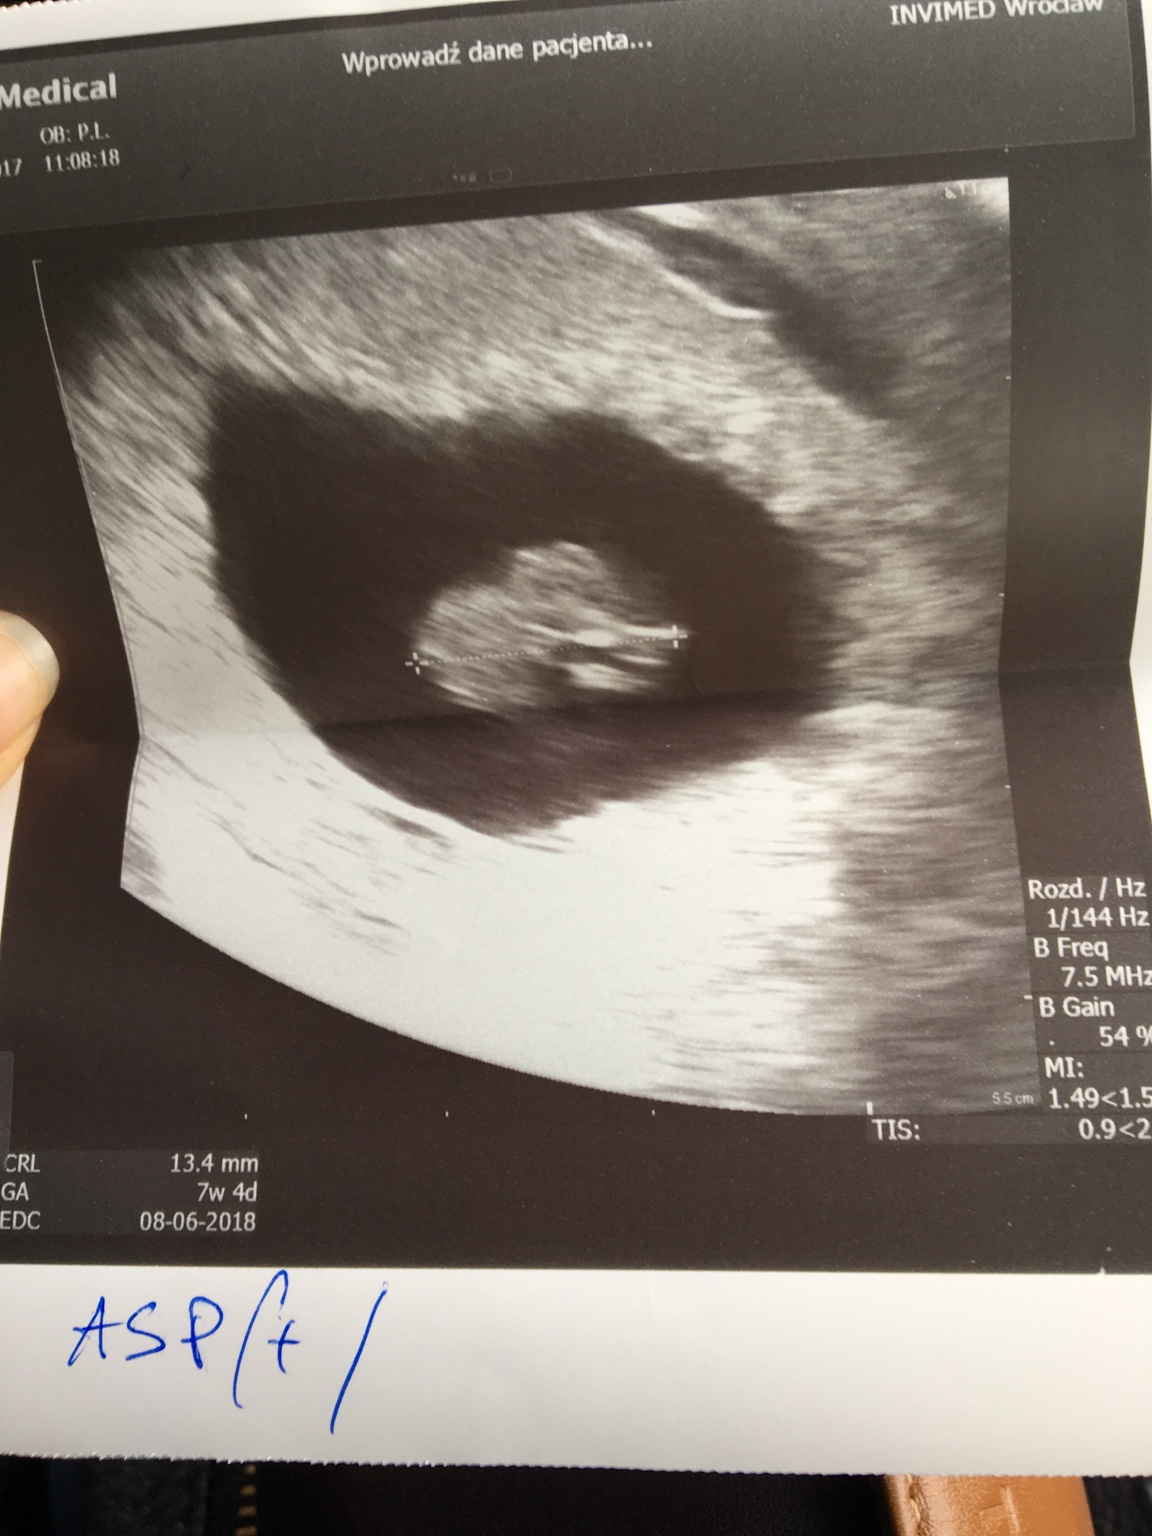

Ja tez chciałam dziś dołączyć [emoji6]choc czytam Was od pierwszej strony, to sie bałam bo trochę niepewna sytuacje mam ale co ma bYc to bedzie... No i boje sie,ze zaraz zamknięcie wątek [emoji6] Po krotce. Z mężem staramy sie BardO długo, leczymy sie we Wrocławiu. W marcu straciłam dzidzie w 6tc1d a dziś juz trochę odetchnęłam 7tc4d i termin na 08.06 przeddzień moich urodzin. Strasznie sie cieszę ale równie okropnie sie boje kolejnej straty, która BardO zle zniosłam [emoji29] pozdrawiam i przedstawiam mojego gagatka , który nie daje mi odetchnąć na dłużej niż jeden dzień po usg [emoji12]